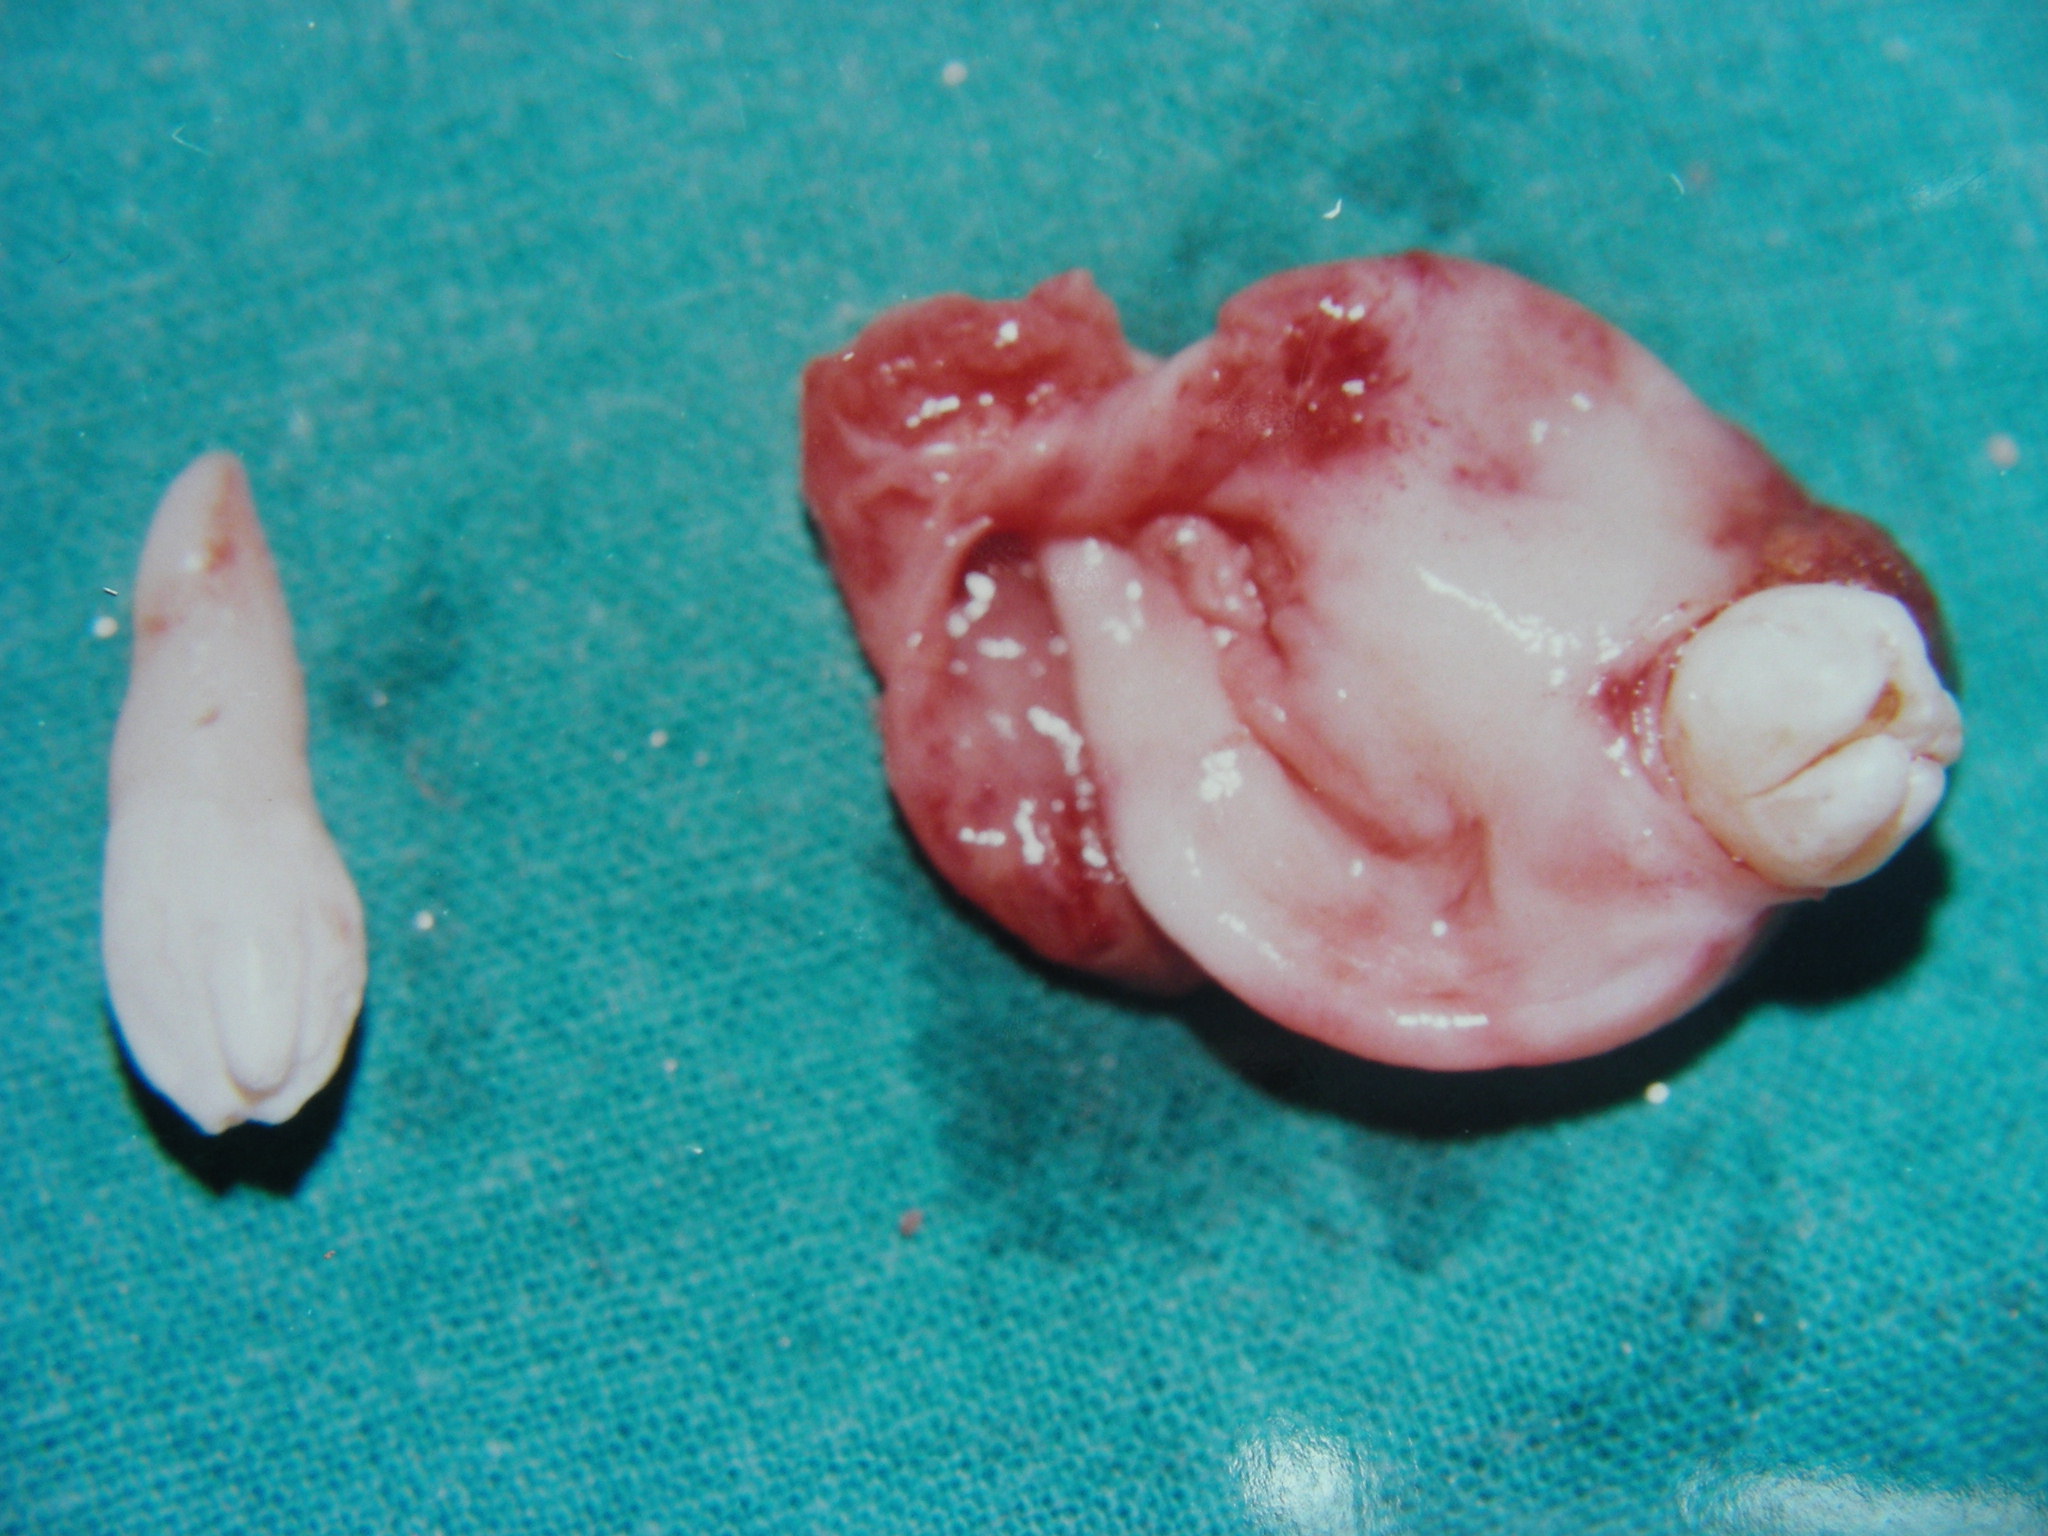

Dentigerous cyst is a developmental odontogenic cyst associated with unerupted teeth, odontomes or supernumerary teeth. About 95% of dentigerous cysts involve the permanent dentition and only 5% are associated with supernumerary teeth. Supernumerary teeth should be examined very carefully to prevent possible effects on adjacent regular teeth and possible cystic development . Dentigerous cysts are usually slow-growing lesions and may attain a considerable size with minimal or no symptoms. Ameloblastoma, mucoepidermoid carcinoma, and squamous cell carcinoma have also been reported to arise from the lining epithelium of dentigerous cysts, indicating the pluripotentiality of their cells. Early detection and removal of such cysts is therefore important to reduce potential morbidity. A rare case of a twelve year old boy with two supernumerary teeth, of which one was associated with dentigerous cyst is described here along with the treatment strategy employed for the patient.